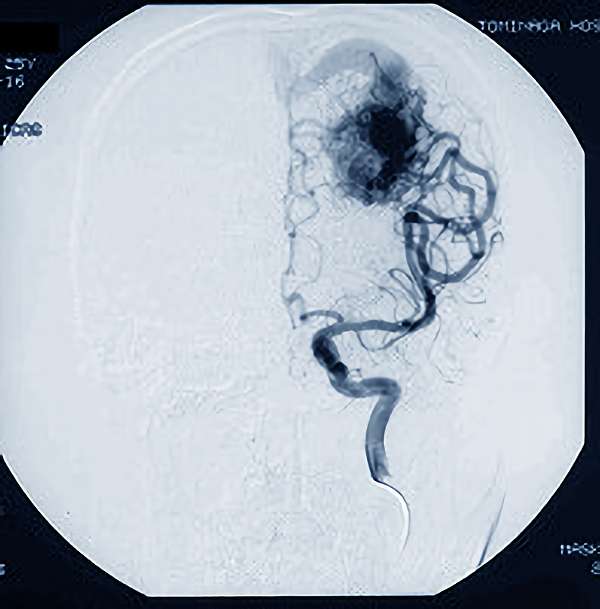

No.359 手術後

出血既往があり。2回の手術前血管内手術の後に、

Lateral transpeduncular approachにより再々出血予防を目的に

摘出手術を行う。完全摘出であることを確認した。

手術による合併症や後遺症なしで退院した。経過良好。